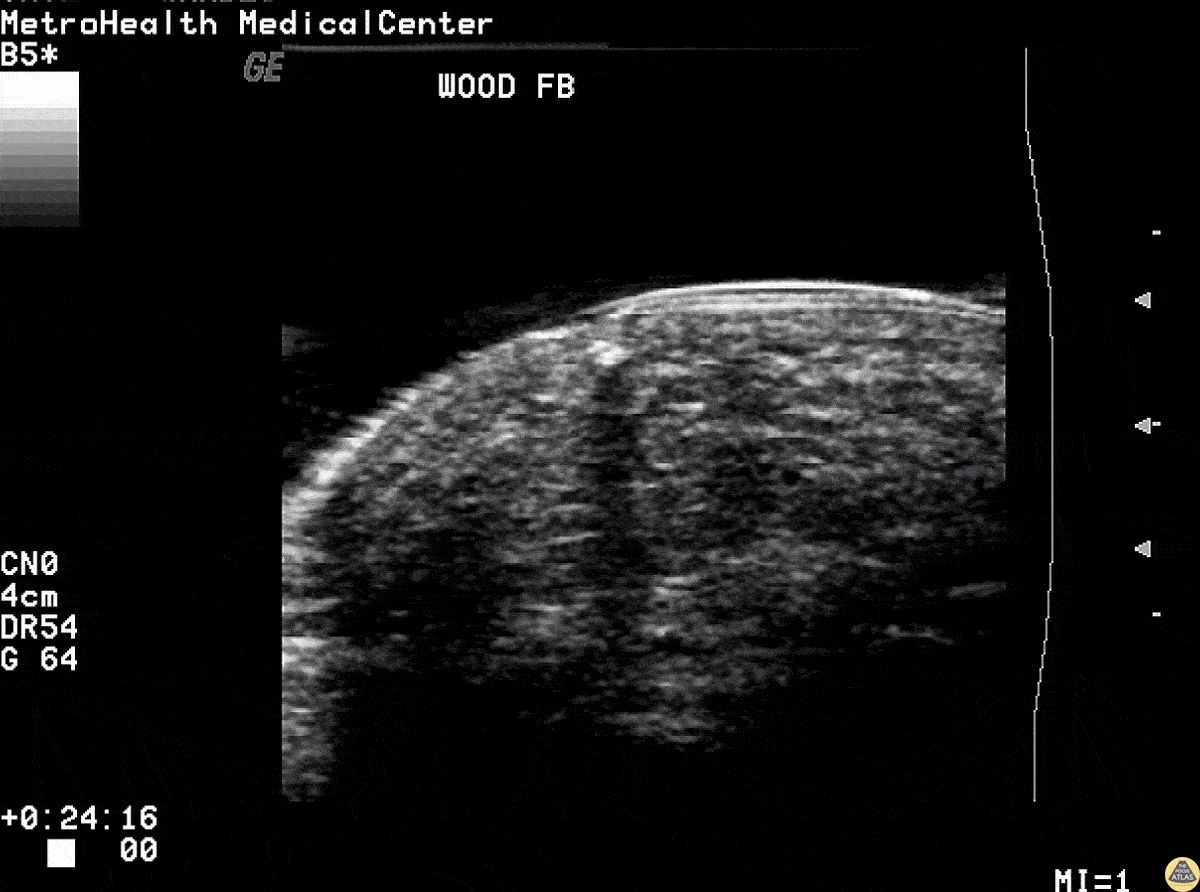

Wooden splinter in the fingertip of a patient. Ultrasound revealed the foreign body with posterior acoustic shadowing present. Image courtesy of Robert Jones DO, FACEP @RJonesSonoEM Director, Emergency Ultrasound; MetroHealth Medical Center; Professor, Case Western Reserve Medical School, Cleveland, OH View his original post here